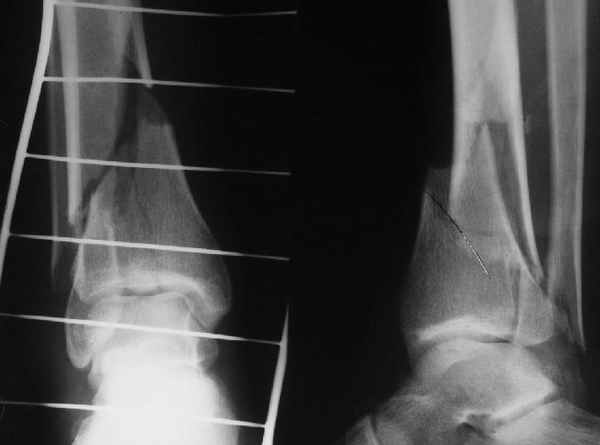

Классически показанием для locked nail яв-ся зоны BC CD, до появления LCP показания к locked nail несколько расширялись в зоны AB и DE

Аргументы: перелом достаточно низкий, трудно будет ввести 3-и блок. винта, а учитывая характер перелома на 2-х дистальных винтах я бы не рекомендовал немедленную полную нагрузку.

АМ> Аргументы: перелом достаточно низкий, трудно будет ввести 3-и блок.

АМ> винта, а учитывая характер перелома на 2-х дистальных винтах я бы не

АМ> рекомендовал немедленную полную нагрузку.

Положим, и с 2 винтами она к 2 месяцам была бы тут вполне реальна. Кроме того, есть возможность ввести винты мимо гвоздя (Poller), и таки разрешить раннюю полную нагрузку (что еще зависит от массы тела пациента и диаметра винтов). А уж если сопоставить стоимость отечественного гвоздика и пластины Synthes... Если бы на порядок более дорогая железка давала на тот же порядок лучший результат... ;-)